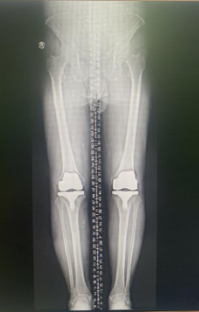

左图:左腿 (术前),右图:左膝(换关节后)

左膝关节置换手术后,老人的膝关节疼痛完全缓解,膝关节功能得到很大改善。